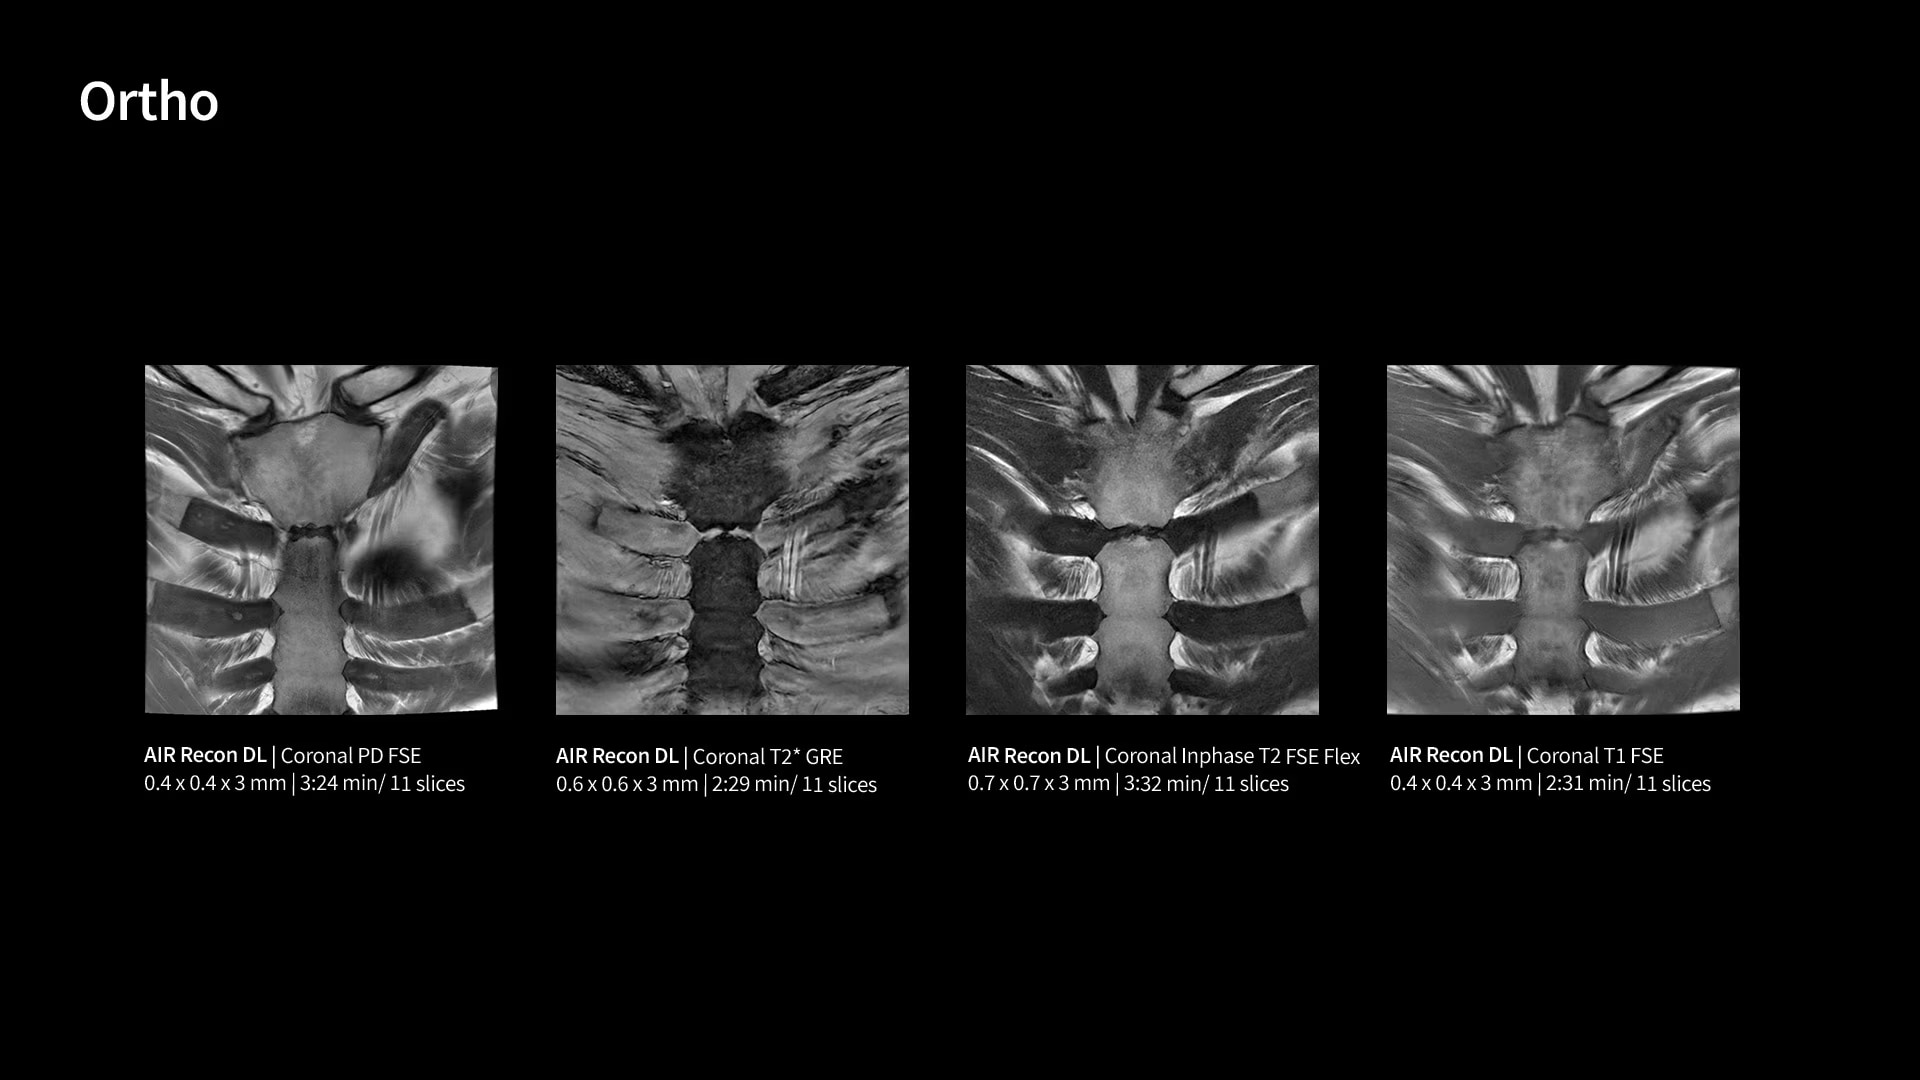

Within cardiovascular diseases, the functional assessment of the heart is an essential imaging application. SIGNA Sprint is powered by built-in AI technologies—Sonic DL™, AIR Recon DL and AIR x™—enabling high-quality imaging even in the most demanding anatomies.

With GE HealthCare's comprehensive suite of deep-learning solutions integrated into SIGNA Sprint, you can unlock the full potential of your MRI system. No need for complicated patient setups or imaging protocols. The exceptional intelligence of our AI solutions offer multiple benefits, with AIR Recon DL giving pin-sharp images, Sonic DL accelerating scans up to 12x, and AIR x enabling automated slice placement. All helping to enhance your department’s workflow efficiency, increase patient throughput, and get the diagnostic clarity you need, faster.¹ Meaning you can spend more time on what truly matters—personalized patient care, enabling optimized treatment plans and treatment response monitoring—ultimately, supporting better clinical outcomes.